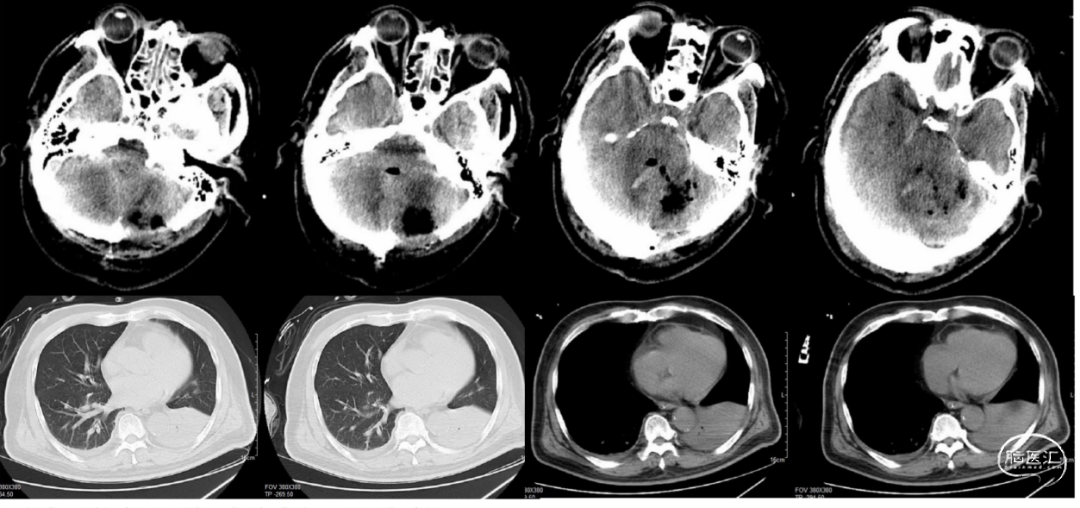

患者2天前(4月6日)晚饭后出现头晕,口齿含糊,行走不便,至当地人民医院就医,急诊就诊期间出现喷射样呕吐数次,随后出现意识不清,急诊头颅CT提示:左侧小脑半球脑内血肿形成,出血破入脑室系统及蛛网膜下腔,急诊行“双侧脑室外引流+小脑血肿清除+去骨瓣减压术”,术后转ICU,机械通气,降颅压,抗感染等治疗,术后患者持续昏迷,患者家属为进一步治疗转来我院,急诊拟“小脑出血”收住我科。既往有高血压病史。入院查体:体温:37.2℃,昏迷,GCS 1+T+1,双侧瞳孔直径2mm,对光反射迟钝,头部两根脑室外引流管,双侧引流通畅,引流出血性液体,后枕部伤口稍有渗出,予换药,去骨瓣处张力中等。两肺呼吸音粗,可及痰鸣音,气管插管,机械通气,心率:94次/分,心律齐,血压:222/99mmHg,腹软,四肢肌力查体不配合,肌张力不高,双侧巴氏征阳性。辅助检查:2021-04-08我院头颅及胸部CT提示:颅脑术后改变,术区积气积液,脑室系统少许积血,两侧额颞部少许硬膜下积血积液(图1)。左下肺支气管塞伴左下肺实变考虑,两侧少量胸腔积液。